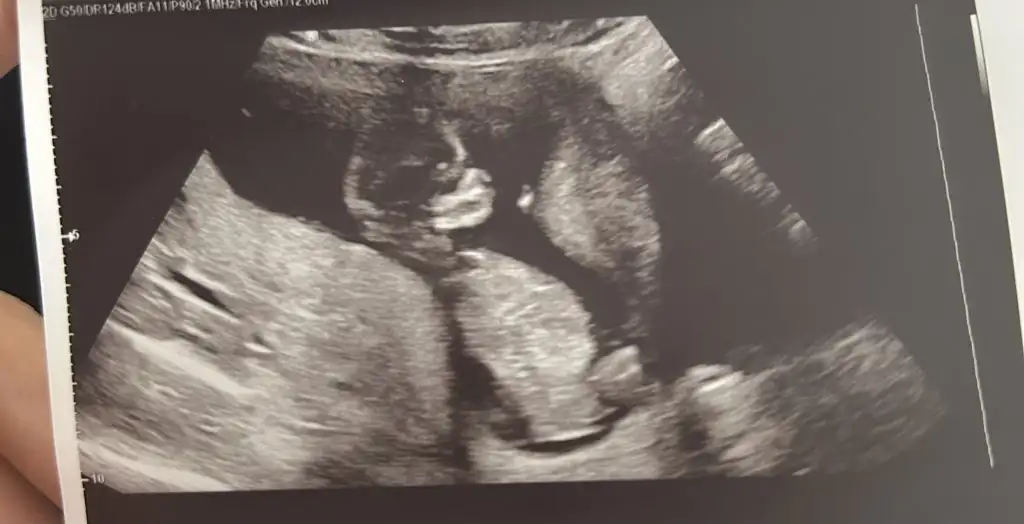

Yaa maşallah herşey yolundaysa yeterBiz kontrolden geldik her şey yolunda gidiyor çok şükür sadece bu kız hiç poz vermiyor sadece el sallıyor

Bende yemek istiyorum resmenYaa maşallah herşey yolundaysa yeterO minik ellerı yerım